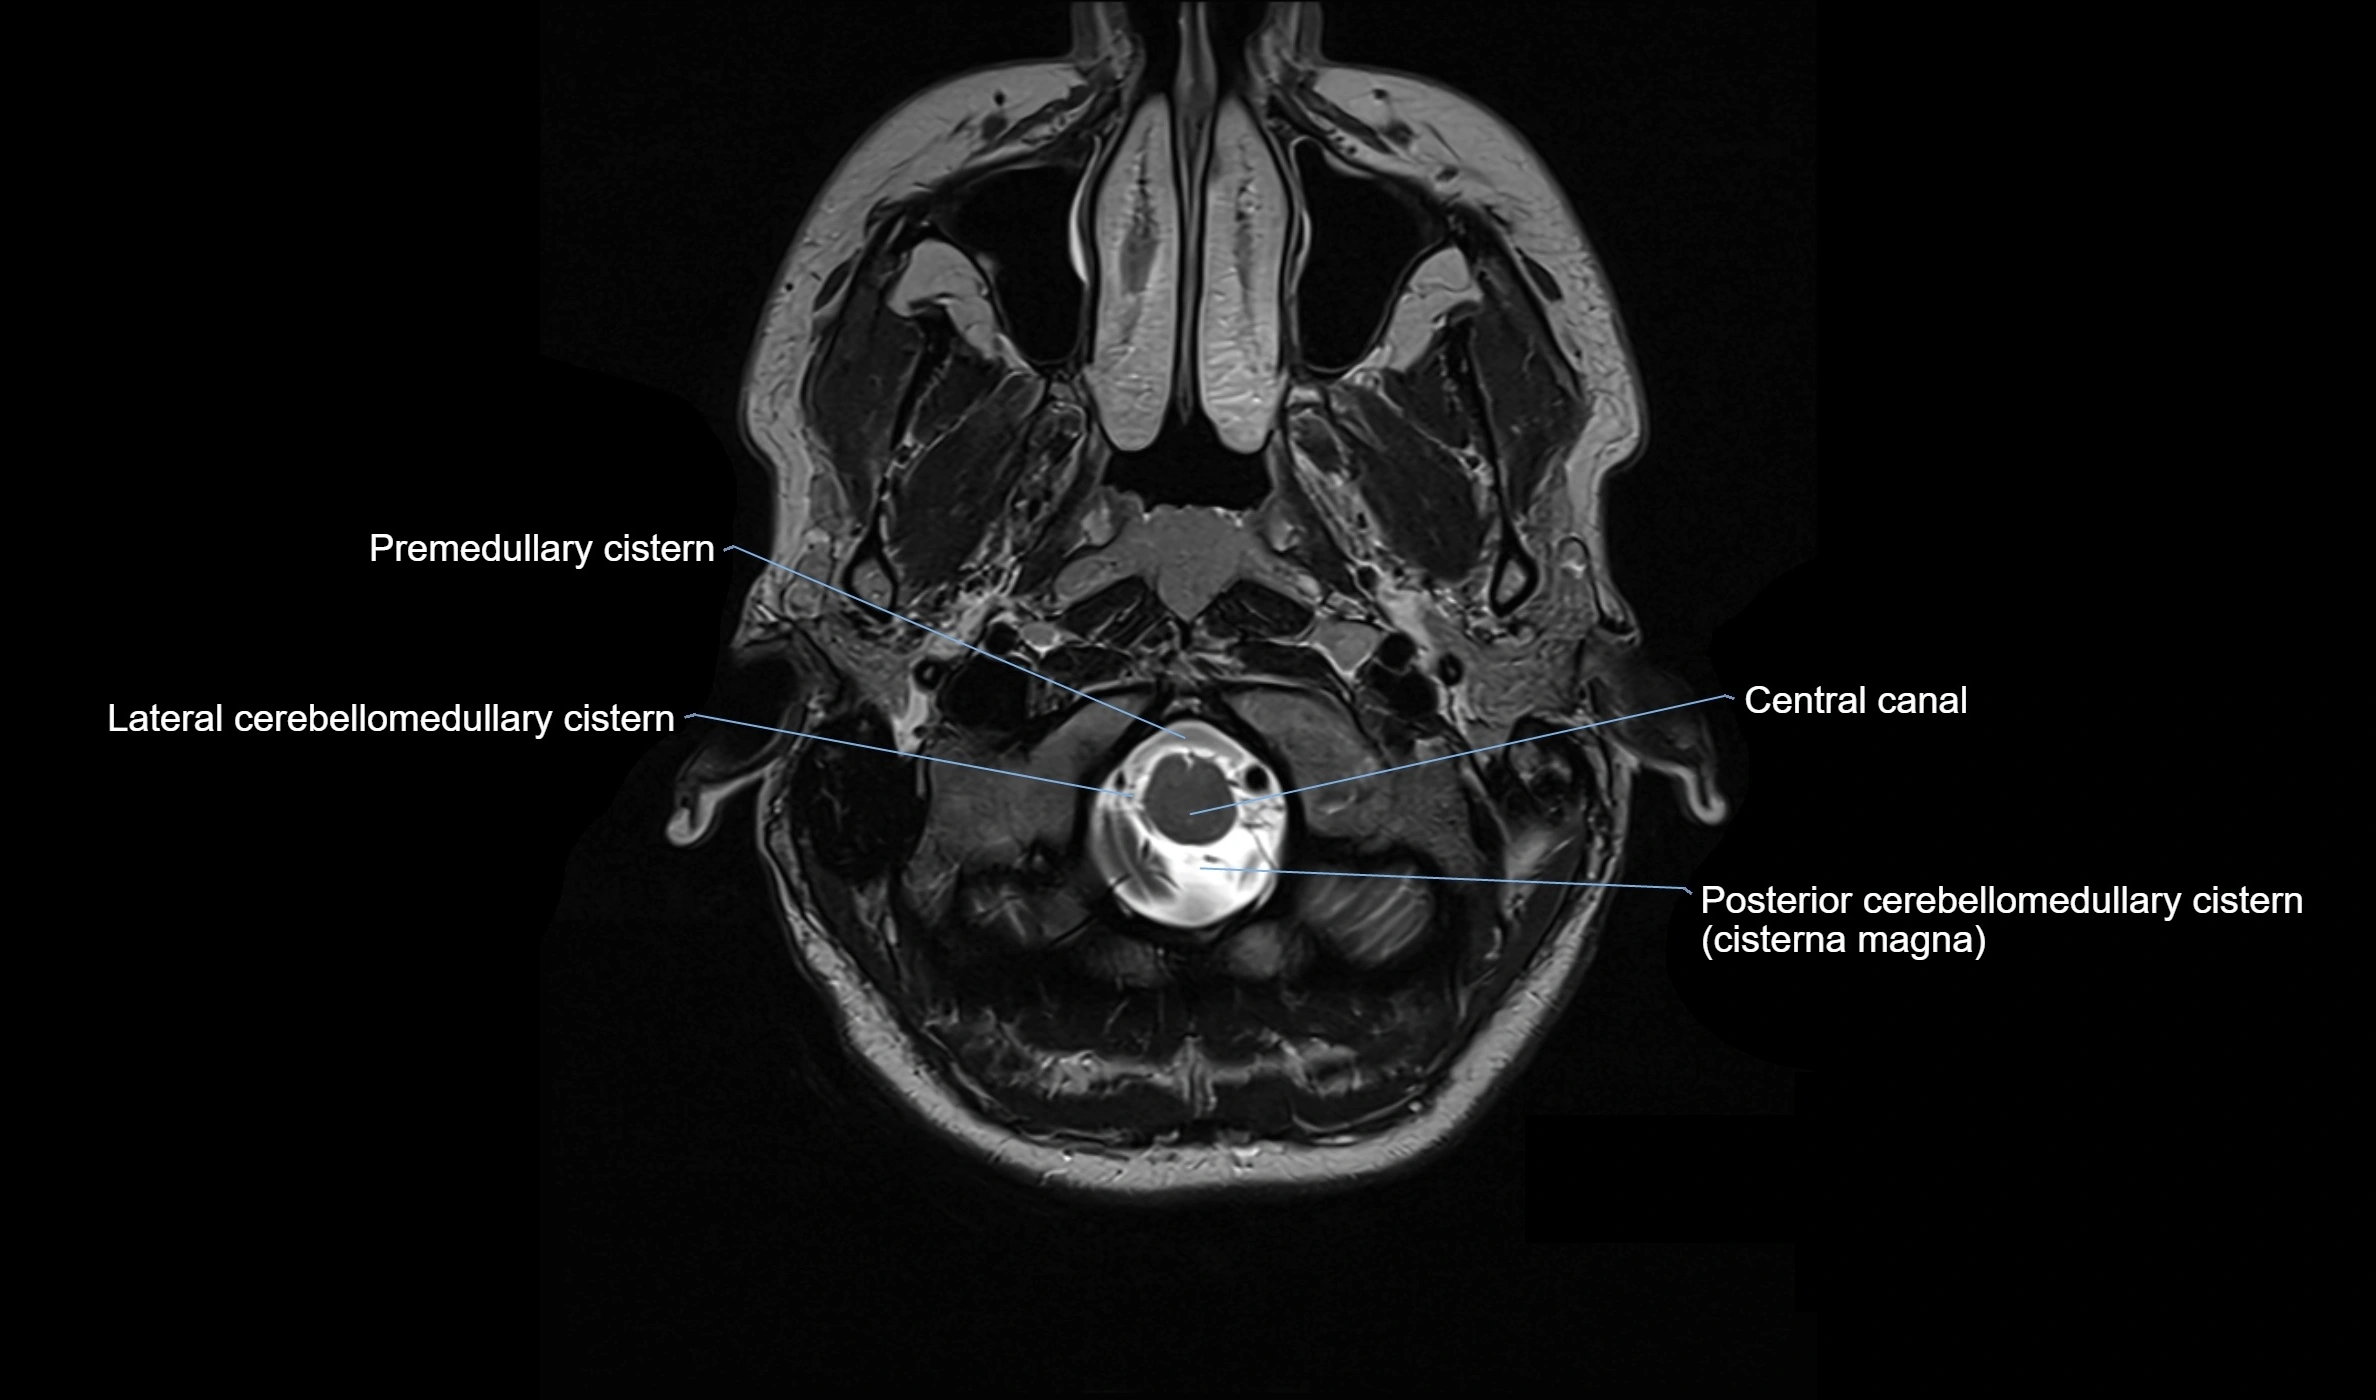

image